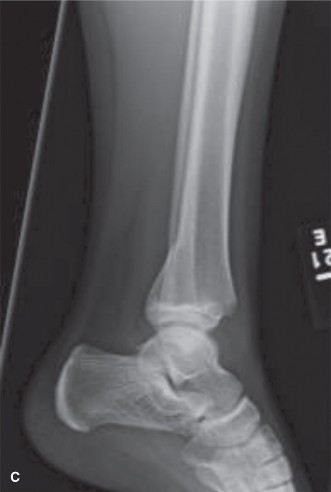

Tillaux fragment. Coincidentally, a 13-year-old male (a player for the opposing team) is in the next bed in the emergency room, awaiting evaluation of a left ankle injury that was sustained in a similar fashion later in the game. Upon your evaluation, his skin is closed, his foot and ankle are swollen, and he is able to actively flex and extend his toes with minimal discomfort. His initial radiographs are shown ( Fig. 10–15A – C ). Based on the available imaging you diagnose this patient with a** ** (choose the correct group of answers).

Figure 10–15 A–B

Figure 10–15 C

1. Triplane fracture; Salter–Harris III on sagittal view; Salter–Harris II on anteroposterior (AP) view

2. Triplane fracture; Salter–Harris II on sagittal view; Salter–Harris III on AP view

3. Triplane fracture; Salter–Harris III on sagittal view; Salter–Harris III on AP view

4. Tillaux fracture; Salter–Harris III on sagittal view; Salter–Harris II on AP view

5. Tillaux fracture; Salter–Harris II on sagittal view; Salter–Harris III on AP view

Discussion

The correct answer is (B). Classically, triplane fractures have the radiographic appearance of a Salter–Harris II fracture on lateral radiographs and of a Salter–Harris III fracture (this is the Tillaux fragment) on coronal imaging.